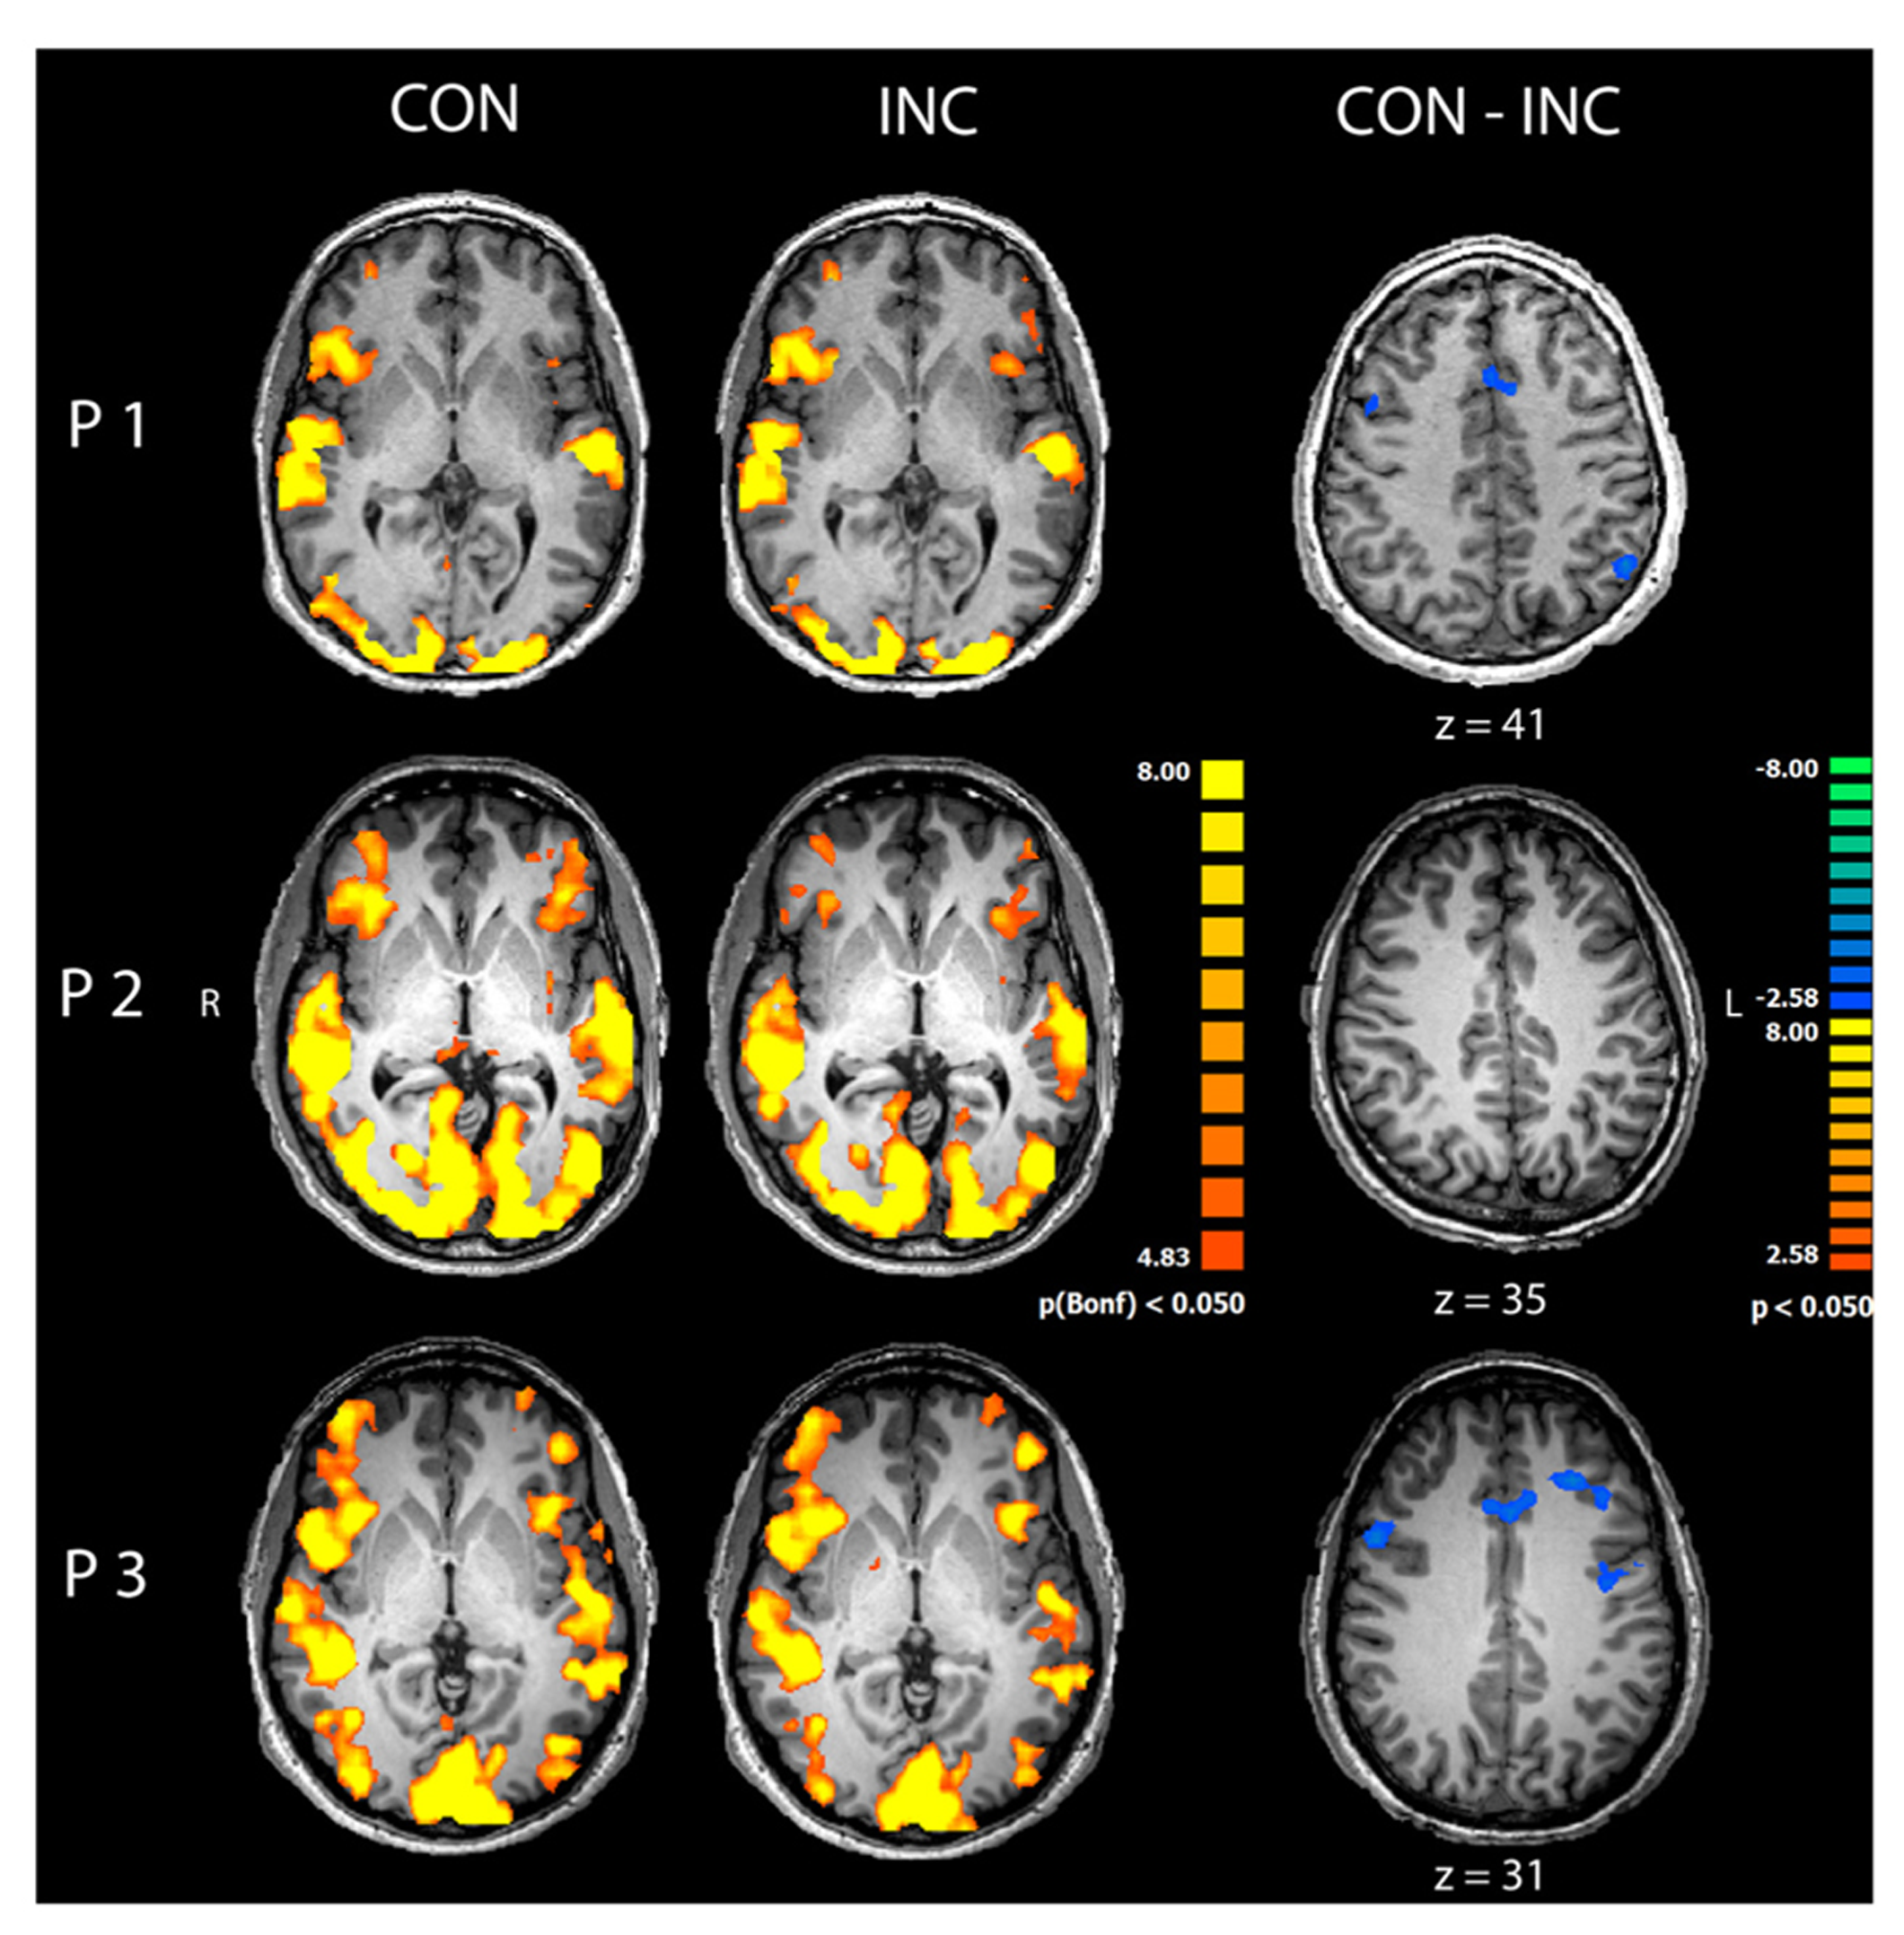

Congruent and INC trials compared to baseline yielded significantly increased activity in bilateral visual, auditory, frontal and motor areas (p < 0.05, Bonferroni corrected; see Figure 3, CON and INC). The comparison of CON and INC trial revealed significantly higher activation for INC trials in ACC and dorsolateral-prefrontal cortex in two out of three participants (Figure 3, CON-INC; p < 0.05; cluster-threshold corrected).

FIGURE 3

Comparison of congruent and incongruent trials. Congruent (CON) and incongruent (INC) trials elicited highly significant widespread activations in visual and auditory cortices as well as motor and medial frontal areas in participants P1–P3 (p < 0.05, Bonferroni corrected). Incongruent compared to congruent trials induced significantly higher activity in mediofrontal and dorsolateral regions in participants P1 and P3 (CON-INC, p < 0.05, cluster-threshold corrected).